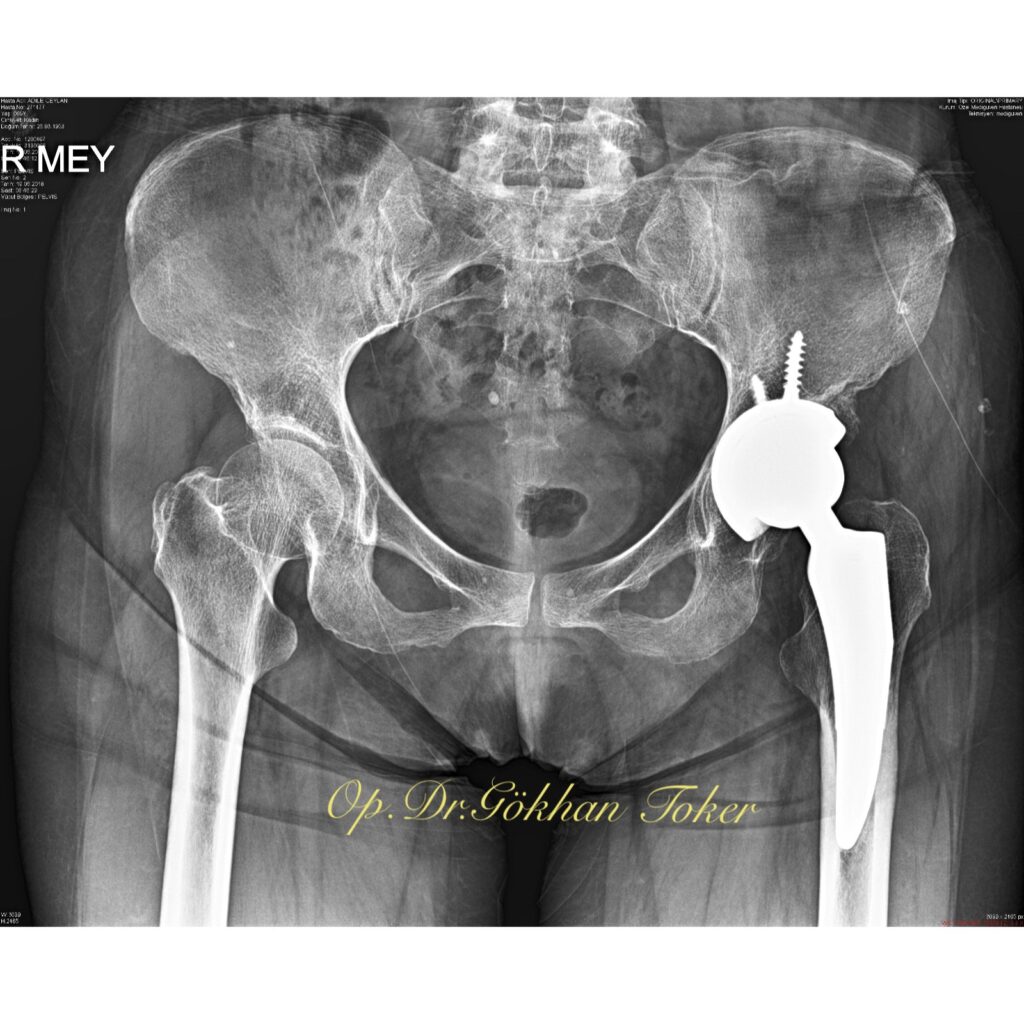

V.K.